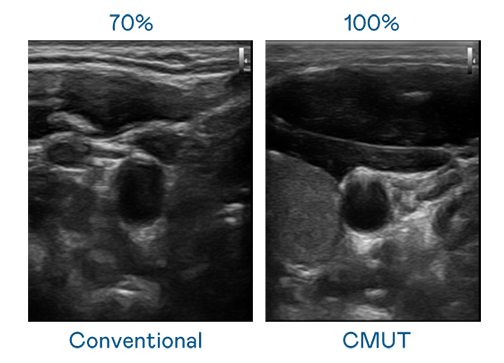

CMUT 技术是一种用电容式微机电元件来产生超音波讯号的技术。与传统 PZT 压电式技术相比,CMUT 频宽增加 30%,更宽频的超音波讯号让影像解析度大幅提升,是实现高影像品质医疗超音波扫描、促进精准医疗发展的关键技术。

超音波影像的解析度高低,首先取决于探头能发出的讯号频宽。贝斯特 CMUT 可提供高清晰的超音波讯号,提供高频宽、高灵敏度、影像纹理细节更高的超音波影像,协助医护人员缩短影像判读时间及利用精准的医疗影像进行诊断。